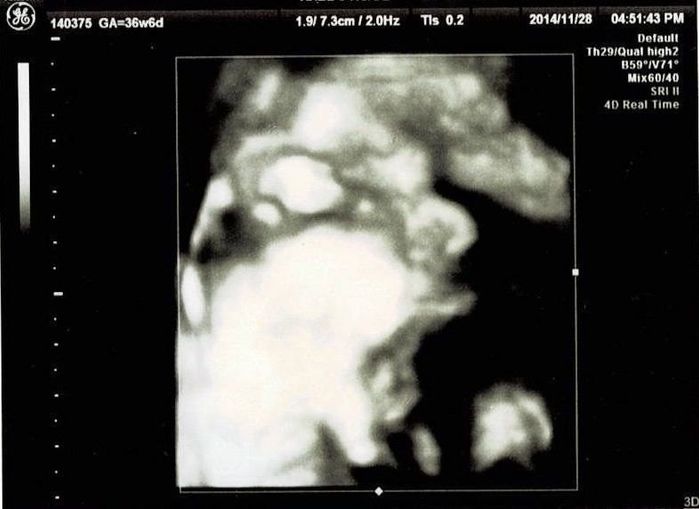

妊娠36週目エコー写真 NST実施 エコー中に赤ちゃんが大あくび!

ノンストレステストを受けました。検査中におなかの張りが計測されたようですが、私はその感覚が分かりませんでした。張りに気づかなかったことで、万が一、お産の兆候がわからなかったらどうしようと不安に。赤ちゃんは3Dエコーをしました。エコーをしているときに、なんと赤ちゃんが大あくび!あくびもするなんて本当に普通の赤ちゃんと変わらないのだなという気持ちに。ほっぺもふっくらとして、やっぱり輪郭はお父さんそっくり!